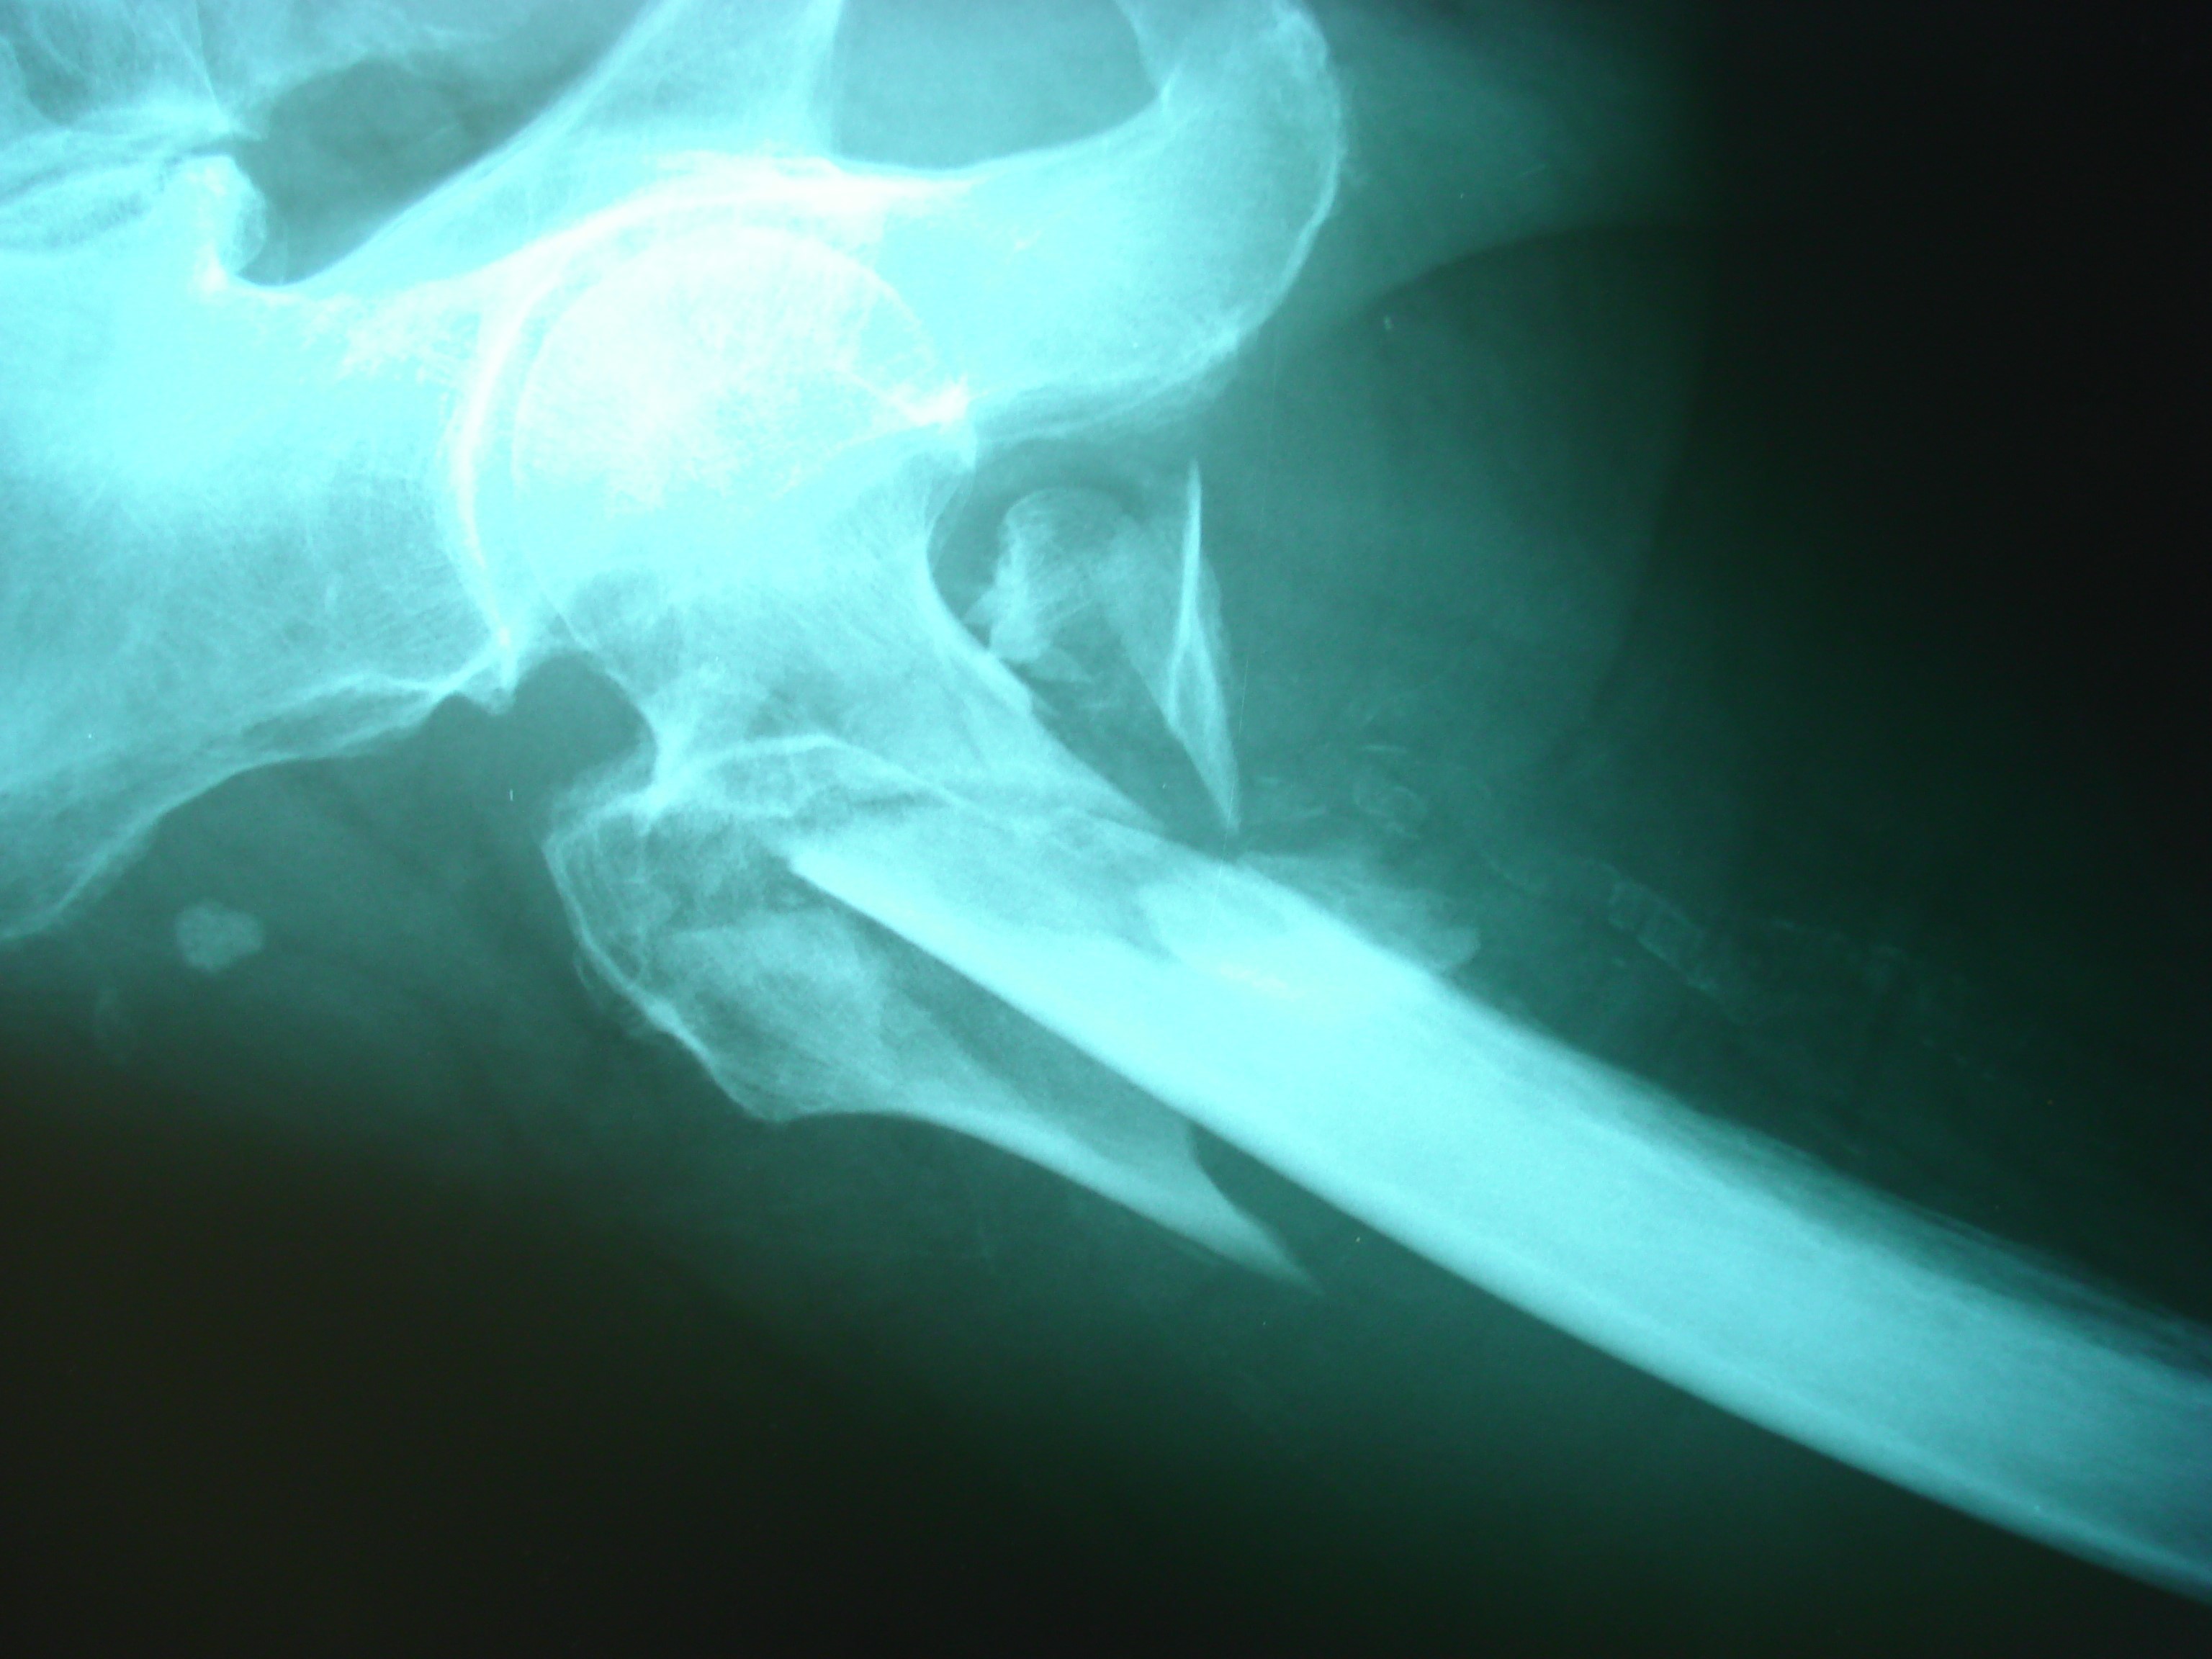

Kalça eklemini oluşturan uyluk kemiği ve onun uzantısı olan top şeklindeki femur başını birleştiren femur boyun kısmında ve boynun altındaki trockanterik bölgedeki kırıklar kalça kırığı adını almaktadır. Yaşlılıkta kemik erimesine bağlı olarak, sık görülen önemli bir sağlık sorunu olarak karşımıza çıkmaktadır.

Kırık uçları yer değiştirmiş, yani tam kırık olmuşsa, hasta yürüyemeyeceği ve şiddetli ağrısı olacağından dolayı hekimin tanıyı koyması çok kolaydır. Çünkü o taraf bacak kısalmış ve dışa dönük pozisyondadır. Röntgen ile kırık tipi belirlenir ve ona göre tedavi edilir.

Kalça bölgesinde kırığın yeri ve şekli, hastanın yaşı, yürüme potansiyeli olup olmadığına göre tedavi seçilmektedir. Uyluk kemiğinin üst kısmındaki ( femur boynu) kırıklarda hasta genç ise kırığın iyileştirilmesine yönelik tedaviler uygulanır. Kırık Tedavisi sonrası ise, kırık kaynayıncaya kadar ameliyatlı ayağa tam yük verdirilmez.